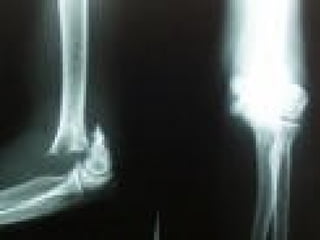

CLASIFICACIÓN PARA LAS  EPIFISIOLISTESIS SALTER HARRIS